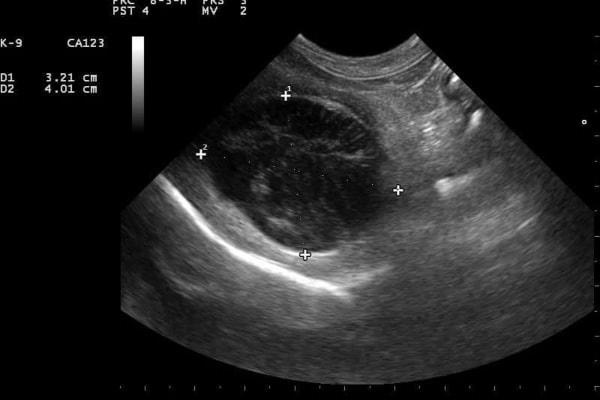

در موارد افزایش آنزیمهای کبدی، تصویربرداری از کبد تقریباً همیشه جواب میدهد. سونوگرافی شکم اطلاعات بیشتری نسبت به رادیوگرافی شکم در اختیار دامپزشک قرار میدهد. مزیت سونوگرافی در این است که میتوان اندازه و شکل کبد را ارزیابی کرد و ناهنجاریهایی مانند تومور، سنگ صفرا یا انسداد مجاری صفراوی را بررسی کرد. همچنین، سونوگرافی میتواند تغییرات نامحسوسی را نشان دهد که احتمال وجود بیماریهای زمینهای دیگر مانند پانکراتیت یا سندرم کوشینگ را مشخص میکند.

سونوگرافی کیسه صفرای سگ – تجمع مخاط غلیظ به دلیل افزایش آنزیم ALP